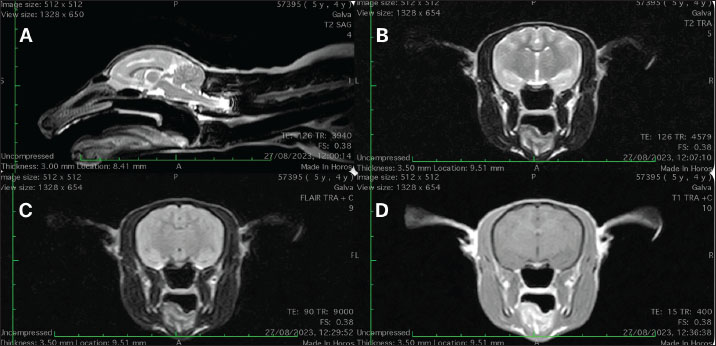

MRI scan was performed using a Hitachi Aperto Lucent 0.4 T (Hitachi Medical Corporation, Tokyo) open-field scanner. The animal was placed in a human knee coil in dorsal recumbency. A standard small animal head protocol was applied that consisted of T2-weighted sequences in sagittal, transversal, and dorsal planes, T1-Weighted Fast spin ech pre- and post-contrast sequences were also acquired in three planes. In addition, fluid-attenuated invertion recovery (FLAIR) was acquired in the transversal plane. Gadobutrol (Gadovist®, Bayer, HealthCare Pharmaceuticals, Ontario) at 0,1 mmol/kg dose, was used as a contrast agent. No structural abnormalities, nor pathological contrast media uptake in the brain or surrounding structures were detected (Fig. 1). Regrettably, cerebrospinal fluid collection for further diagnostic evaluation was not performed. Recovery from anesthesia was uneventful.

Fig. 1. (A) Mid-sagital T2W; (B) T2W, (C) FLAIR and (D) T1 post-contrast images at the level of thalamus. No structural abnormalities, nor pathological contrast media uptake in the brain or surrounding structures were detected.